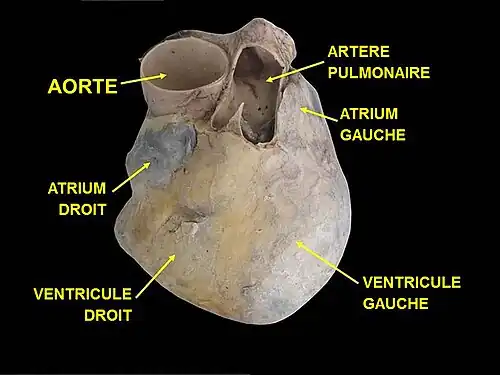

Morphologie

Dans le corps humain, le cœur se situe dans la région thoracique (poitrine), où il occupe plus précisément la portion antéro-inférieure du médiastin entre la seconde et le cinquième espace intercostale. Il est situé sur la ligne médiane, un peu décalé à gauche de telle sorte que deux tiers de sa masse sont situés du côté gauche. C'est la position dite de lévocardie, qui est normale sauf en cas de malformation congénitale ayant inversé la position des autres organes entre la gauche et la droite (situs inversus). D'autres malformations de naissance peuvent placer le cœur à droite (dextrocardie) ou au milieu (mésocardie (pt))[1]. Le cœur est contenu dans la cavité péricardique qu'il occupe entièrement, et il est entouré par les poumons (recouverts de la plèvre) de chaque côté, le diaphragme en bas, le sternum en avant, l'œsophage en arrière et les troncs artériels (aorte et artère pulmonaire) en haut.

Le cœur est un organe fibromusculaire de forme grossièrement conique ou pyramidale avec une base et un sommet, l'apex (ou pointe). L'axe base-apex est orienté approximativement en avant et à gauche selon un angle de 45°, et légèrement vers le bas. On décrit au cœur les faces postérieure (ou basale), inférieure (ou diaphragmatique), antérieure (ou sterno-costale), et latérales (ou pulmonaires) gauche et droite.

Le cœur d'un adulte mesure environ 12 cm de la base à l'apex. Son diamètre transversal maximal est de 9 cm et son diamètre antéropostérieur est de 6 cm. À titre de comparaison, sa taille est d'environ 1,5 fois la taille du poing de la personne[réf. nécessaire]. Un peu moins gros chez la femme que chez l'homme, il mesure en moyenne chez celui-ci 105 mm de largeur, 98 mm de hauteur, 205 mm de circonférence. Le cœur d'un adulte pèse environ 300 g chez un individu masculin et 250 g chez un individu féminin, soit en principe, respectivement 0,45 et 0,40 % de la masse corporelle totale.

Le cœur est un muscle creux contenant deux parties séparées bien qu'accolées l'une à l'autre : le « cœur gauche » et le « cœur droit ». Ces deux « cœurs » sont situés côte-à-côte dans l'axe base-apex, séparés par une paroi globalement verticale et orientée dans l'axe du cœur. Chacune de ces deux parties est subdivisée en deux chambres ou cavités, l'atrium (ou oreillette) vers la base et le ventricule vers l'apex. Ces deux cavités sont séparées par une valve ; on distingue ainsi la valve mitrale, entre l'atrium et le ventricule gauches, et la valve tricuspide, entre l'atrium et le ventricule droits. L'organisation est symétrique entre le cœur gauche et le cœur droit, bien que le cœur gauche soit plus volumineux. Afin que le ventricule droit puisse répondre à ses contraintes de pression dilatatrice, la trabécule septo-marginale solidarise les différentes parois ventriculaires[2].

La paroi séparant les cavités gauche et droite est appelée septum. On distingue le septum interventriculaire entre les ventricules gauche et droit, le septum interatrial entre les atriums gauche et droite, et le septum atrioventriculaire entre les atriums et les ventricules. La terminologie ne doit pas être source de confusion vis-à-vis des positions relatives ; en effet, du fait de l'axe globalement oblique vers la gauche, le cœur gauche est grossièrement situé en arrière et à gauche du cœur droit, exception faite de l'apex, principalement constitué de l'extrémité du cœur gauche.

Base du cœur

La base du cœur est la surface extérieure située dans la partie supérieure et postérieure du cœur. Elle est orientée vers l'arrière et légèrement à droite et en haut. Elle est de forme quadrangulaire et constituée par la face postérieure des atriums.

Elle est limitée en haut par le tronc pulmonaire et en bas par la partie postérieure du sillon coronaire qui la sépare des faces inférieure et latérale gauche du cœur.

Elle reçoit les quatre veines pulmonaires de chaque côté dans l'atrium gauche et les veines caves supérieure et inférieure dans l'atrium droit.